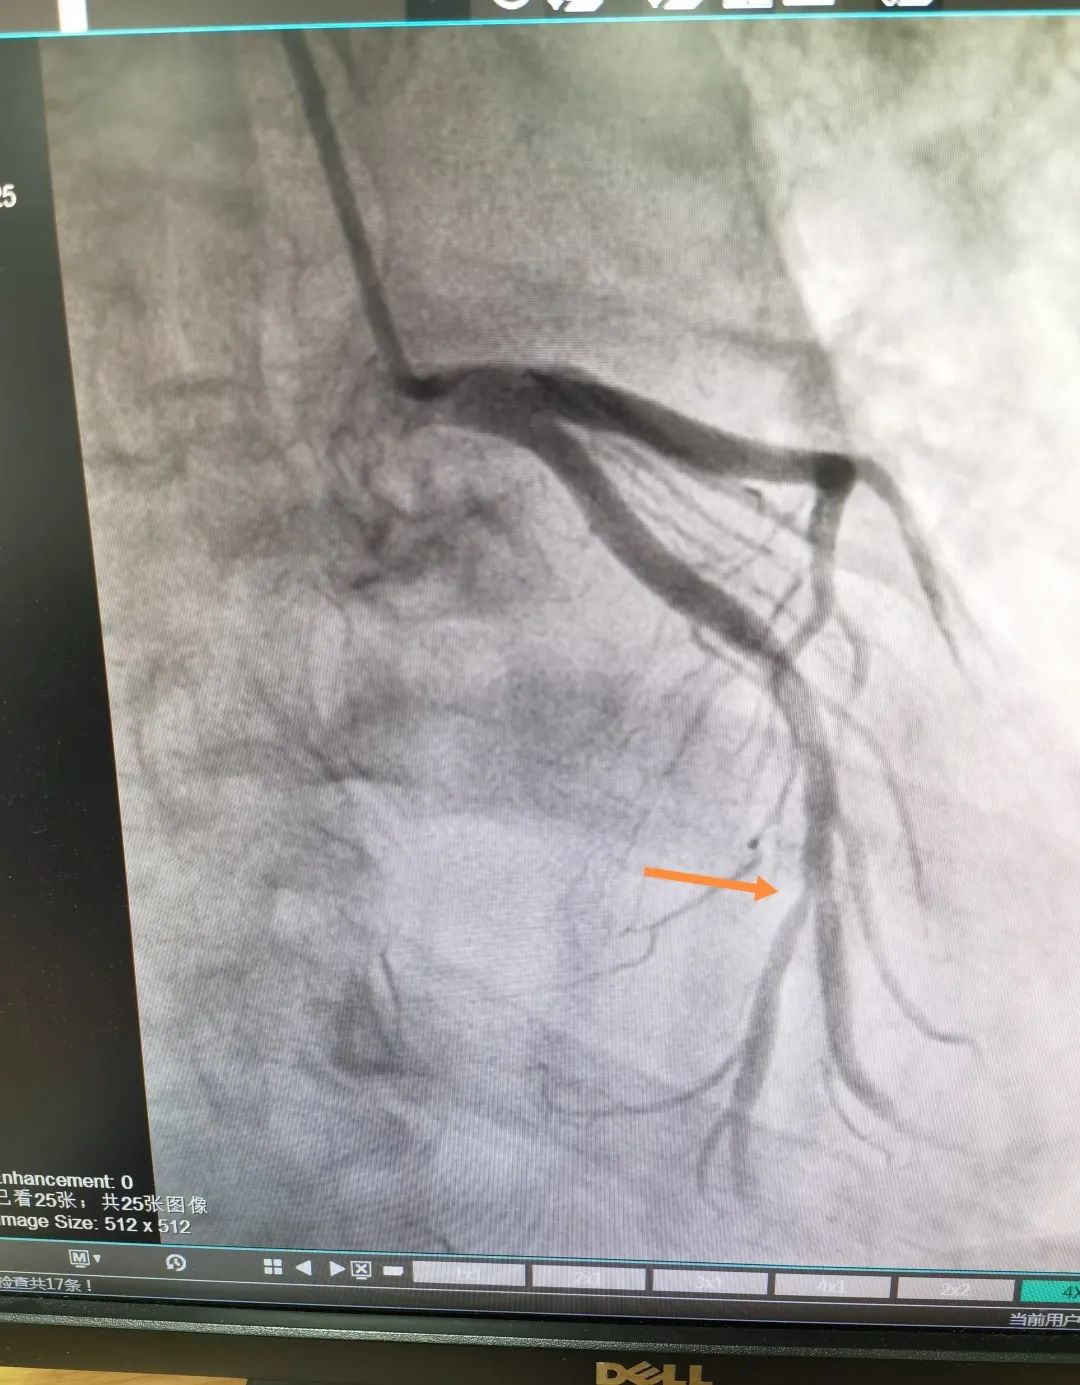

近日,一位 72 岁男性患者反复胸痛一年,加重一个月后来我院心内科治疗,心内科支部书记俞海峰主任医师为其实施在 QFR(定量血流分数)指导下的药物球囊治疗,真正做到精准治疗、绿色治疗。

术中的 QFR 依靠冠脉造影三维重建技术和血液动力学系统,并融入人工智能血流定量;精确分析狭窄冠脉血管的功能学指标,是无创、精确评估冠脉生理功能指标的「新标准」。

这位患者在 QFR 指导下对于分叉病变使用药物球囊治疗,避免了支架的植入对分叉另外一根血管的压迫,从术前和术后的 QFR 数值来看,手术收到了非常好的疗效。同时该患者不需要长期服用双联抗血小板药物,只需服用双联抗血小板药物一到三个月,因此对于特定病变和特定人群具有不少优势。

术前影像